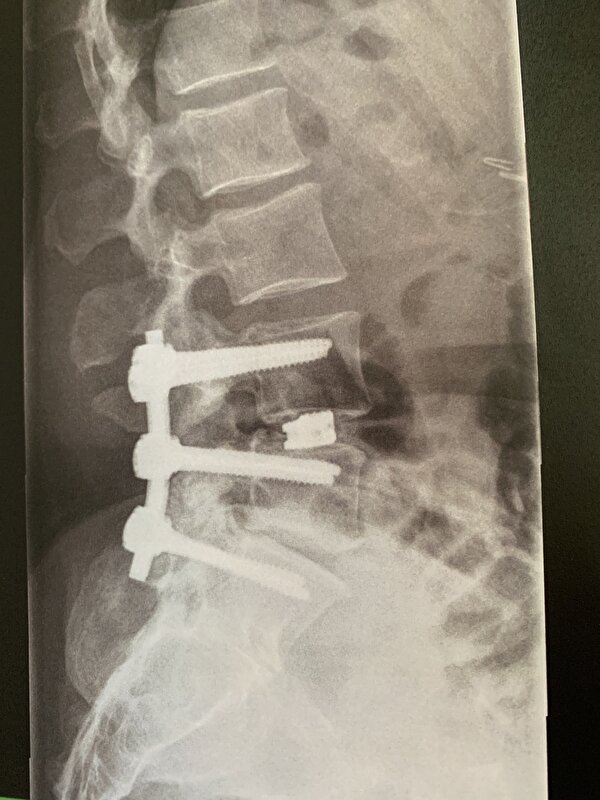

Jet schreef:Nobel, hoort daar ook nog een tussenwervelschijf te zitten die er nu niet of nauwelijks meer is? En zie ik scoliose?

Nobel01 schreef:Jet schreef:Nobel, hoort daar ook nog een tussenwervelschijf te zitten die er nu niet of nauwelijks meer is? En zie ik scoliose?

Inderdaad geen tussenwervelschijf meer, scoliose, artrose, en als je goed kijkt zie je ook kissing spines op de foto.

Ook staat de onderste wervel niet meer in lijn, die was aan het afglijden.

Inmiddels is mijn rug vastgezet, geen pijn meer.

Artrose, zit die ook bij die overgang waar de tussenwervelschijf weg is? Als ik nog een keer kijk lijkt daar wel een haakje te zitten. Op zich heel fijn dat je nu pijnvrij bent, maar het zal je wel beperkingen opleveren.